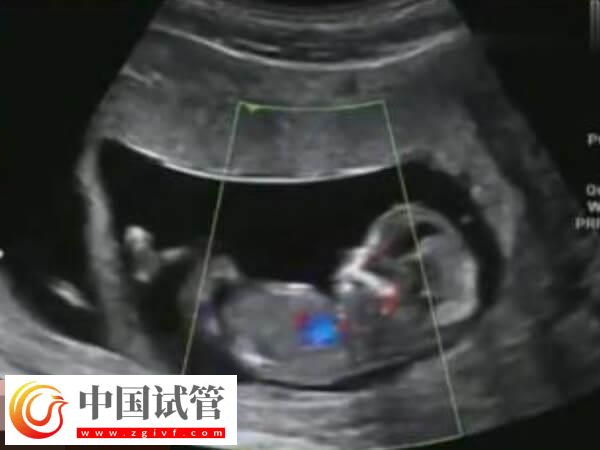

试管婴儿移植成功后,女性需要定期去医院接受孕产检查。这些检查包括血液化验、超声波检查等,以确保宝宝的健康发育和母亲的身体状况。此外在孕期中要遵循医生的建议进行适当的锻炼。